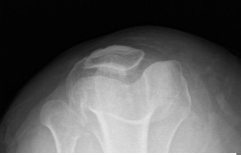

X-ray and MRI were presented in the office. Found vertical tear at the free edge margin of the posterior horn medial meniscus, with mild undersurface/free edge fraying of the body segment. Mild medial femorotibial compartment chondral loss. Mild patellofemoral compartment chondral wear, preferentially over the medial aspect of the compartment.

Lateral patellar tilt with mild lateral positioning of the patella. These findings may be seen in the setting of patellar malt racking. Features which may be seen in the setting of iliotibial band friction syndrome.

Patella Skyline